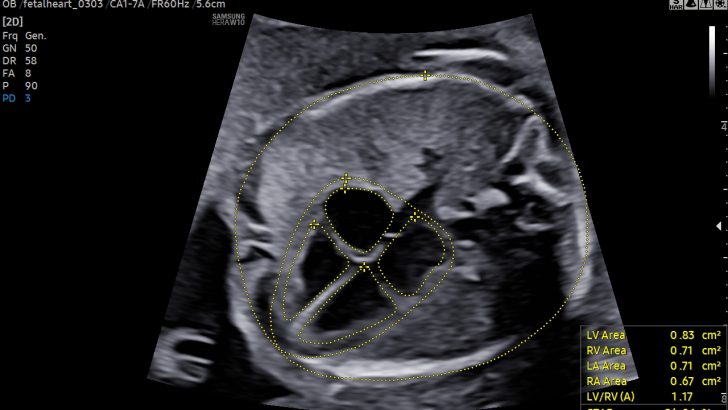

‘Biometry Solution’ recognizes images such as the fetal head, abdomen, lower extremities and others and measures the fetal growth and development while the ‘Fetal Heart Solution’ recognizes the view of the fetal heart, annotates the images and measures the necessary fetal heart structures for a thorough fetal heart anomaly assessments.

The feature automatically recognizes and annotates the anatomy of the fetal heart and displays measured values when the ‘Fetal Heart Solution’ is executed.